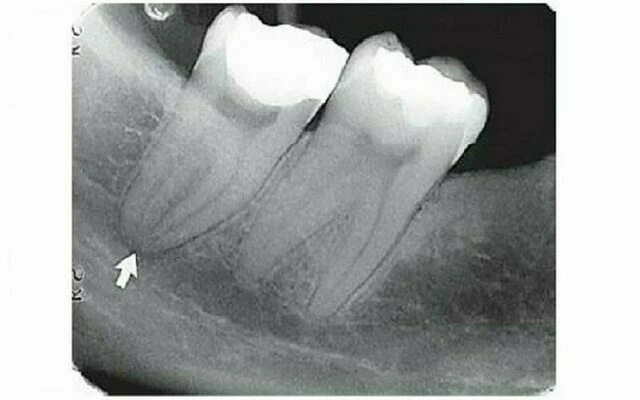

Ống hàm dưới

Hình ảnh X quang của ống hàm dưới là một đường đen với đường biên giới phía trên và dưới cản quang do được tạo nên bởi các phiến xương mỏng bao quanh ống. Đôi khi biên giới chỉ thấy một phần hoặc thấy toàn bộ. Độ rộng của ống khác nhau giữa các bệnh nhân nhưng thường giống nhau ở phần phía trước đến vùng răng cối lớn thứ ba. Đường đi của ống giữa lỗ hàm dưới và lỗ cằm khá rõ. Chỉ có là hiếm khi hình ảnh liên tục phía trước hướng về phía đường giữa có thể thấy rõ trên X quang.

Mối quan hệ giữa ống thần kinh răng dưới với các chân răng dưới có thể khác nhau, có thể tiếp xúc gần với các chân răng cối và chân răng cối nhỏ thứ hai đến việc không có liên quan gì đến các răng sau. Tuy nhiên, ở hình ảnh bình thường thì ống hàm dưới tiếp xúc với chóp răng cối lớn thứ ba, và khoảng cách giữa nó với các chân răng tăng lên khi nó chạy về phía trước. Khi chóp các răng cối có hình chụp chồng lên ống này thì lamina dura có thể bị chiếu tia nhiều, tạo ấn tượng rằng thiếu lamina dura hoặc khoảng dây chẳng nha chu dày lên, tức thấu quang hơn so với mức độ bình thường của bệnh nhân. Để chắc chắn về sự toàn vẹn của răng, cần thực hiện các thử nghiệm lâm sàng khác (chẳng hạn thử độ sống tủy). Vì ống này thường nằm ngay dưới chóp các chân răng sau, thay đổi góc chụp theo chiều dọc ở một phim thứ hai sẽ không giúp tách được hình ảnh của ống và chóp răng.